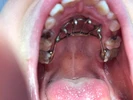

Zirkonyum uygulamalar

Porselen uygulamaları

Laminate veneer